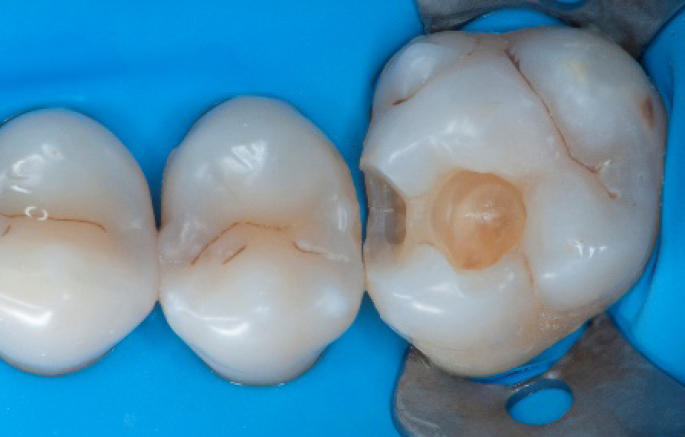

Step 6:

Selective enamel etching procedure with Conditioner2.

Step 7:

Adhesive application with a universal adhesive, Prime&Bond3.

Step 8:

Transformation of class II into class I, restoring the interproximal wall with Spectra ST4 composite in shade A2.